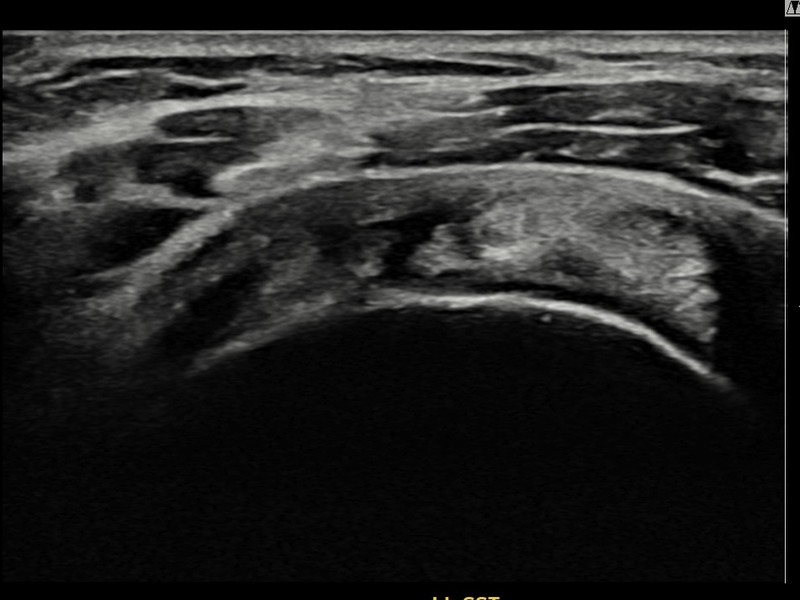

김ㅇㅇ님 · 좌측 극상근건 광범위 부분파열

좌측 어깨 광범위 파열로 수술을 권유받았으나 비수술 치료를 원해 내원하셨습니다. 초음파 검사에서 극상근건 전층에 걸친 광범위 부분파열이 확인되었으며, 어깨인대 축소봉합술 후 구조적 안정화와 기능 회복이 이루어졌습니다.